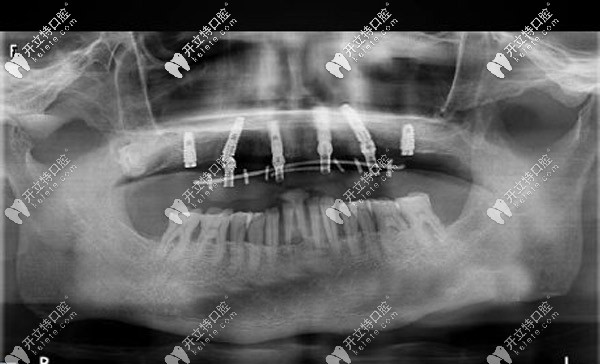

經(jīng)過(guò)口腔CT三維拍片確診,周老先生患有牙周炎,且有牙齦萎縮的情況。羅緣口腔的種植醫(yī)生通過(guò)數(shù)字化動(dòng)態(tài)導(dǎo)航系統(tǒng)在計(jì)算機(jī)上重建口腔頜骨三維立體模型。

與周老先生進(jìn)行溝通后,確定了種植體嵌入位置、數(shù)量、種植深度、植體傾斜角度等等,并采用上頜6顆即刻種植技術(shù),運(yùn)用“數(shù)字化動(dòng)態(tài)導(dǎo)航種植”方案。

口腔種植中的動(dòng)態(tài)導(dǎo)航就像汽車(chē)導(dǎo)航一樣,在顧客進(jìn)行種植牙手術(shù)時(shí),可根據(jù)提前設(shè)計(jì)好的種植方案,通過(guò)顯示屏實(shí)時(shí)直觀地看到種植體植入頜骨的全過(guò)程。

全程監(jiān)控種植位點(diǎn)、角度、深度,能夠避免損傷重要的解剖結(jié)構(gòu)。這樣做可以節(jié)省大量的種植時(shí)間,縮短牙骨暴露在外的時(shí)間,保存了牙骨的活性,有利于植體和牙槽骨的緊密結(jié)合。